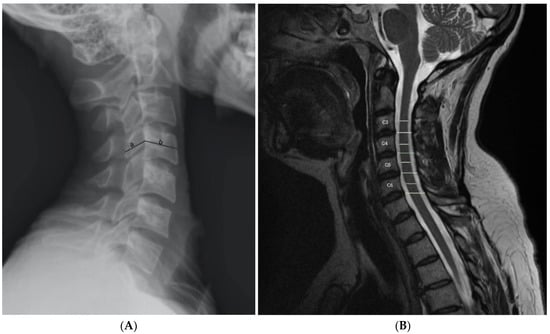

8. Imaging